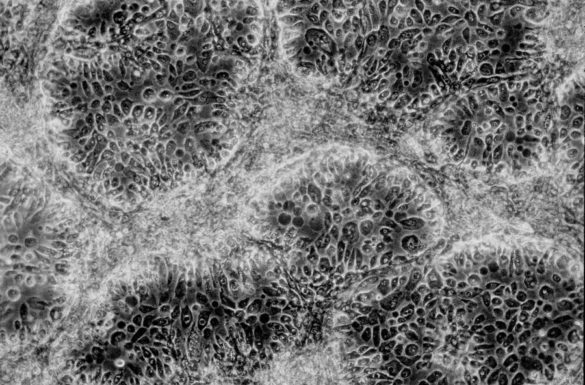

Cancer : le médicament à 475 000 dollars !

475 000 dollars ! J’ai cru halluciner en entendant Thierry Philip, le président de l’Institut Curie, annoncer le prix de ce nouveau traitement contre le cancer qui vient d’être autorisé aux États-Unis. C’était la semaine dernière, durant une conférence que j’animais pour cet Institut et